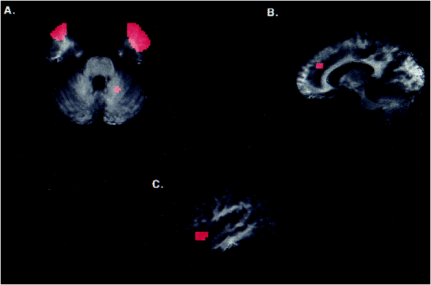

An important corollary question concerns where guilt and forgiveness originate, biologically. Shin et al (2000) looked at PET scans and physiological responses of eight young men in Boston (avg. age of 25) who provided researchers with written descriptions of personal events: one involving the most guilt the participant had ever experienced, and two neutral events. The participants were then read a transcript of their self-described experiences while being scanned and monitored for physiological changes in heart rate, skin conductance (an estimate of emotional arousal in sweat glands), and left lateral frontalis electromyograms (activity in the muscle over the forehead). As expected, the men reported that subjective feelings of guilt increased when read their transgressions, as did shame, sadness, disgust, anger, and fear. However, researchers found that physiological responses did not differ significantly between the guilt and neutral states. The PET scans revealed that regional cerebral blood flow increased in three paralimbic regions of the brain, including the bilateral anterior temporal poles, anterior cingulate gyrus, and left anterior insular cortex/inferior frontal cortex, while decreases were seen in more posterior portions of the left insular cortex. However, the researchers also noted the difficulty in isolating the experience of guilt from other simultaneously experienced emotions (ex. shame, sadness). Nor was the severity of the guilt-related experiences in these young men revealed.

Blood flow increases in the guilt state from PET scan results (A) anterior temporal poles, (B) anterior cingulate gyrus, (C) left anterior insular cortex/inferior frontal gyrus (from Shin et al.)